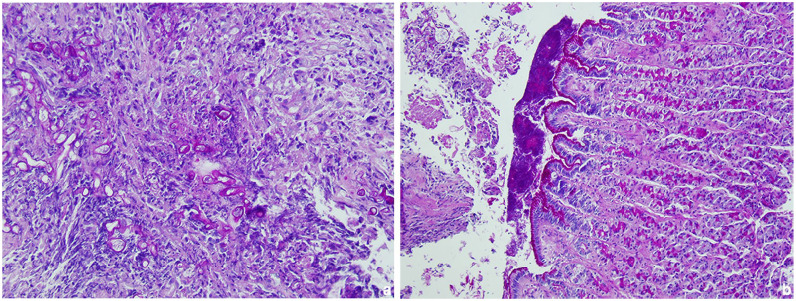

Case summary: This report describes a case of gastric mucormycosis in a young Ragdoll cat with a 5-day history of vomiting. Physical examination detected mild dehydration and tenderness was elicited on abdominal palpation. The results of blood work-up and radiographic study were unremarkable; however, abdominal ultrasonographic examination revealed multiple hyperechoic neoformations at the level of the pyloric antrum, which were confirmed on endoscopic examination. Non-septate hyphae of irregular diameter with a branched appearance were observed on cytology, and histological examination revealed severe diffuse necrotising and granulomatous gastritis with the presence of intralesional fungal hyphae indicative of mucormycosis, which was confirmed by PCR tests. Antifungal therapy with ketoconazole in addition to supportive treatment temporarily improved the clinical condition. Lethargy, fever and abdominal effusion developed in the following days. Cytological examination of abdominal fluid was compatible with septic peritonitis and, given the severity of the condition, euthanasia was opted by the owners. Post-mortem examination confirmed septic peritonitis resulting from perforation of the gastric wall at one of the neoformations of the pyloric antrum.

Relevance and novel information: To the authors' knowledge, this is the first reported case of gastric mucormycosis in a cat. Previous literature includes a case of mucormycosis in a Persian cat affecting only the duodenum. In both the Persian cat and the cat described here, gastrointestinal mucormycosis disease progressed rapidly and was fatal.